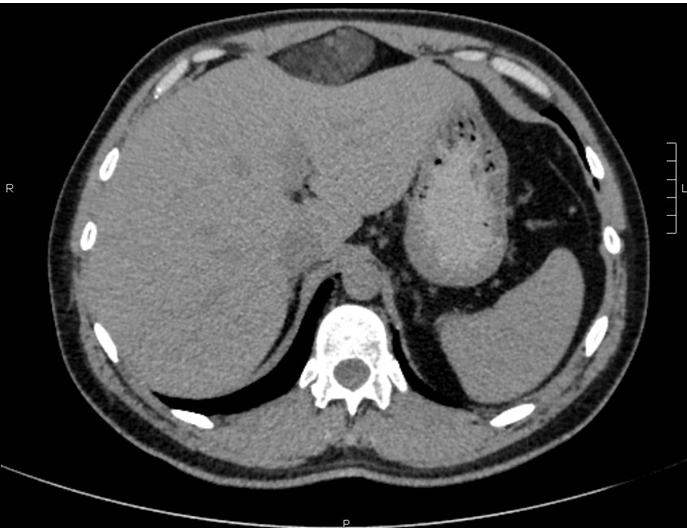

A 41-year-old male was referred to general surgery clinic with cramping epigastric pain associated with waking with an acid-like taste in his mouth. On examination, there was a palpable, hard round mass in his epigastrium. He was investigated with a full blood count, liver and kidney function tests and electrolytes; which were all within normal limits. An ultrasound scan documented a mass just below his xiphisternum, beneath his linear alba, 61x48x31 mm in size, causing mild compression of the liver. This mass was further investigated with a computed tomography scan which demonstrated a lesion reported as vascular in nature with differentials including a vascular malformation, hemangioma or vascular neoplasm (Figure 1).

Figure 1: Computer tomography scan, axial view of mass compressing anterior liver.